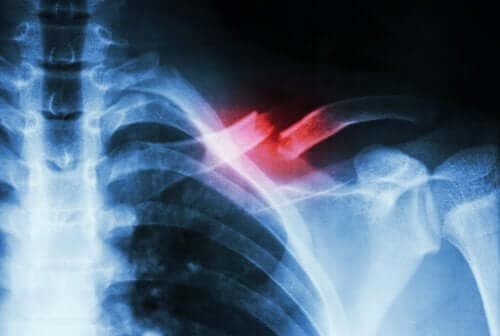

كسور الإجهاد هي كسور صغيرة الحجم تظهر لأسباب أخرى مختلفة عن التعرض للصدمات القوية. فهي إما تظهر بسبب الحركات المتحررة أو بسبب الزيادة المفاجئة في حدة أو سرعة الحركة.

من الصعب تشخيص هذا النوع من الكسور لأنها لا تظهر في الأشعة السينية. ولذلك يحتاج تشخيصها إلى طبيب متخصص وفحوصات معينة للتفرقة بينها وبين الحالات الطبية الأخرى.

معظم إصابات الكسور تحدث بسبب الصدمات أو الضربات. ولكن، في حالة كسور الإجهاد، يكون عادةً المسبب هو الإجهاد أوالضعف.

يحدث الإجهاد عندما يتم الضغط على العضلات عن طريق الحركات المتكررة أو الغريبة. وينتج الضعف عن قصور العظام ونقص العناصر الغذائية.

هذا النوع من الكسور قد يؤدي إلى ألم حاد أثناء تنفيذ بعض الحركات أو الأنشطة البدنية. وهو ما يختفي عادةً مع التوقف عن ممارسة النشاط.

تتكون العظام من مادة تُعرف باسم الكولاجين. هذا هو المكون الذي يسهل عملية إعادة هيكلة العظام عند تعرضها للضغط. يمكن من خلال هذه الوسيلة استيعاب أي أنسجة تالفة، ثم إعادة تشكيلها.

ولكن إذا كان الضغط مستمرًا أو مفاجئًا، يتعدى التلف قدرة الجسم على تجديد الكولاجين. وهو ما يحدث في حالة كسور الإجهاد.